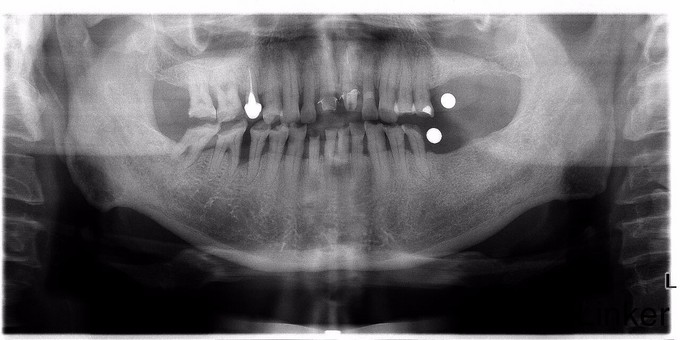

游离缺失牙的种植修复

左侧上下均有缺牙,一直无法咀嚼,要求镶牙

上颌单侧游离端缺失设计对比